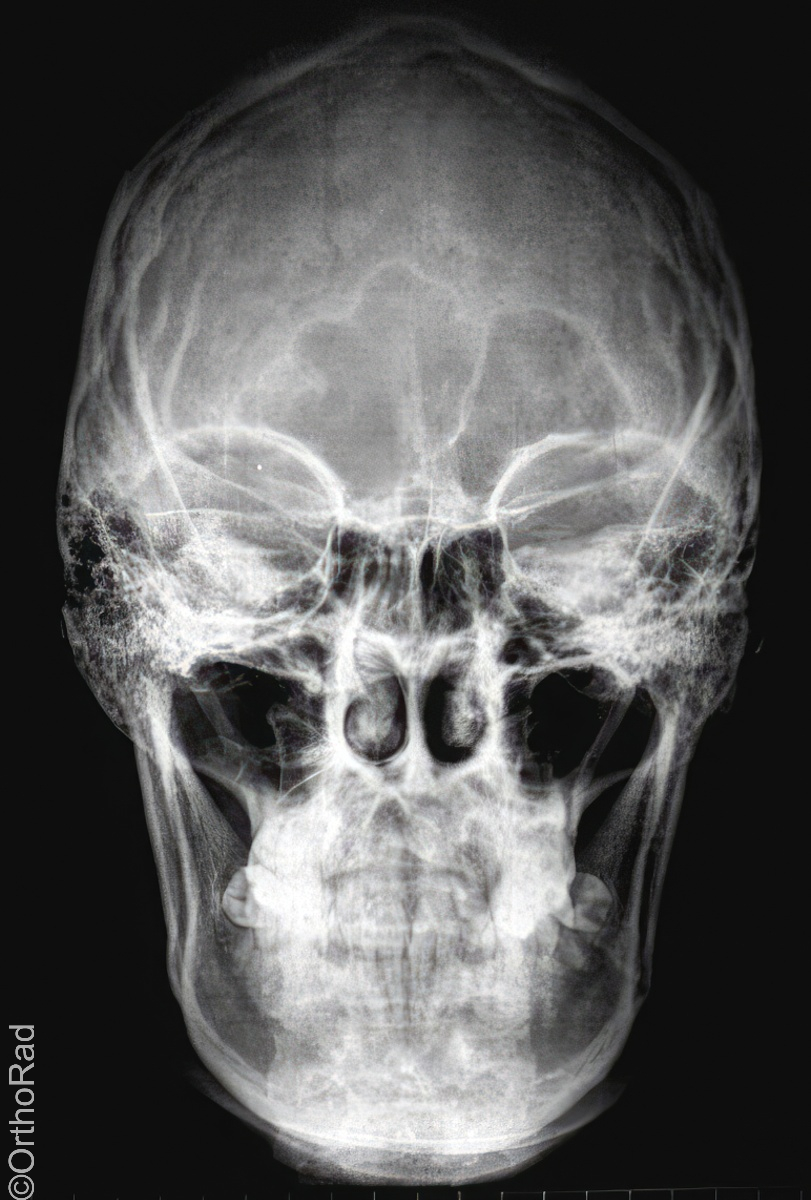

Schädel a.-p.

Fremdkörper-Lokalisation vor MRT, Shuntkontrolle

Symmetrische Abbildung beider Schädelhälften, Nasenscheidewand streng in der Mitte. Die Felsenbeine stellen sich im unteren bis mittleren Drittel der Orbita da. Felsbeinspitzen projizieren sich in die Mitte der Orbita oder eher etwas oberhalb davon.